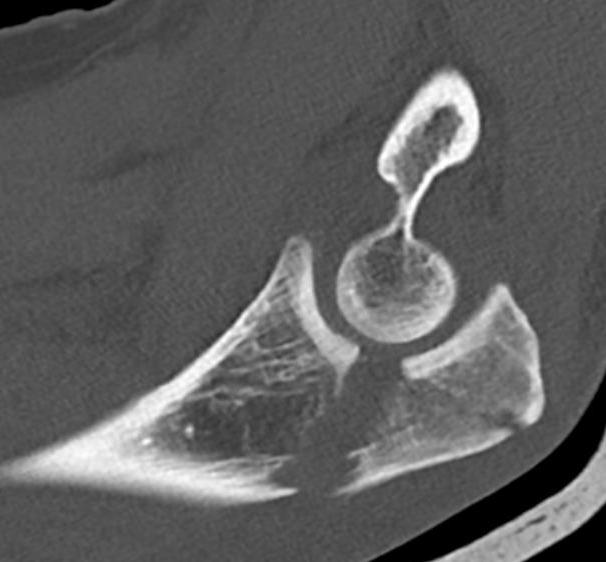

Proximal articular portion of the ulna

- greater sigmoid notch articulates with trochlea

- has a central bare area

Mayo Classification

A: Non comminuted

B: Comminuted

| Type I | Type II | Type III |

|---|---|---|

| Minimally displaced | Displaced | Trans-olecranon fracture dislocation |

| 10% | 85% | 5% |